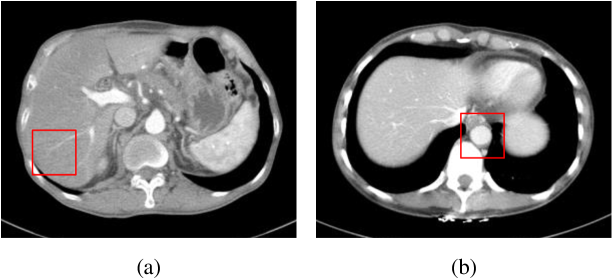

Figure 11: Illustration of the two samples, where the box regions in red were identified as (a) metastasis pancreas and (b) aorta. Their zoom-in comparisons are presented in Figs. 12-13. (WL: 10, WW: 400, source: the AAPM Grand Challenge committee)

Last, we show two representative examples from these evaluations: Fig. 11 presents an overview of the two samples in full-dose, in which their zoom-in crops are compared in Figs. 12-13: Fig. 12 depicts a lesion that is barely noticeable by experts due to its low contrast. Similar to the full-dose references, our method could transfer details more faithfully and maintain the contrast but with an even lower noise level. In comparison, some methods either fail to suppress noise (e.g., WGAN, DU-GAN) or introduce artifacts (e.g., CTformer), making them less reliable in clinical exams. Fig. 13 visualizes the cross-section of the aorta, where the higher uniformity in our result indicates better denoising quality.